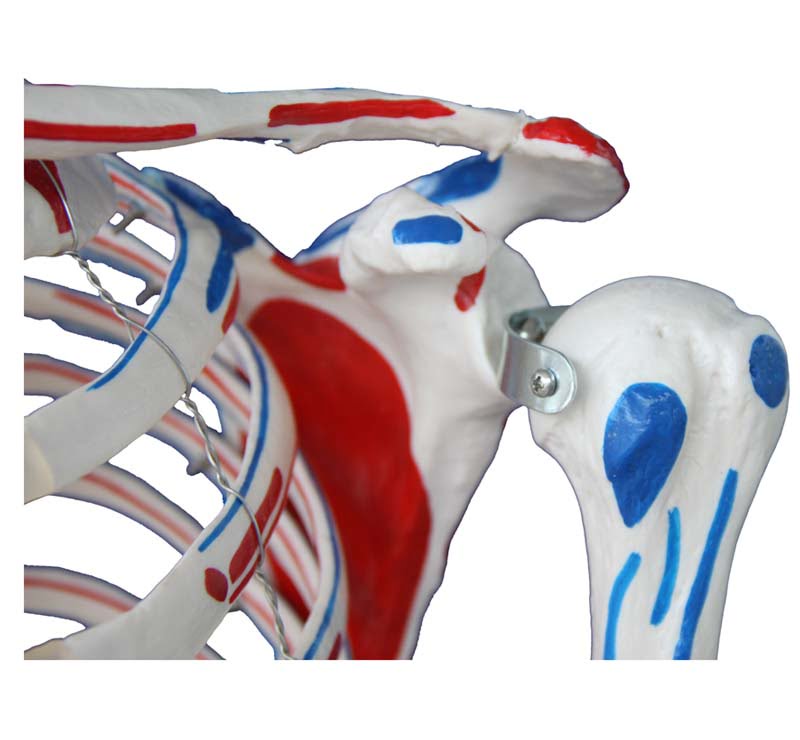

Skeleton with Muscles and Ligaments

Skeleton with Muscles and Ligaments

Τhis model is painted to show the muscles and ligaments. The left side of the skeleton shows the points of origin (red) and the points of insertion (blue) of the muscles.

SPECIFICATIONS

Size: 180cm (Life Size)

Material: PVC

Weight: 14Kg

Base is included.

Skeleton with Muscles and Ligaments

Skeleton with Muscles and Ligaments